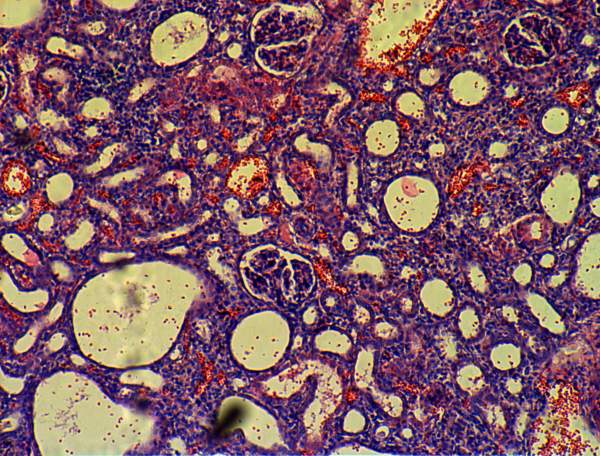

间质性肾炎切片观察